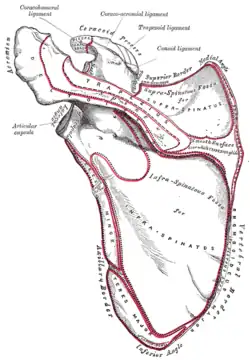

The left shoulder and acromioclavicular joints, and the proper ligaments of the scapula. Anterior view.

The left shoulder and acromioclavicular joints, and the proper ligaments of the scapula. Anterior view.